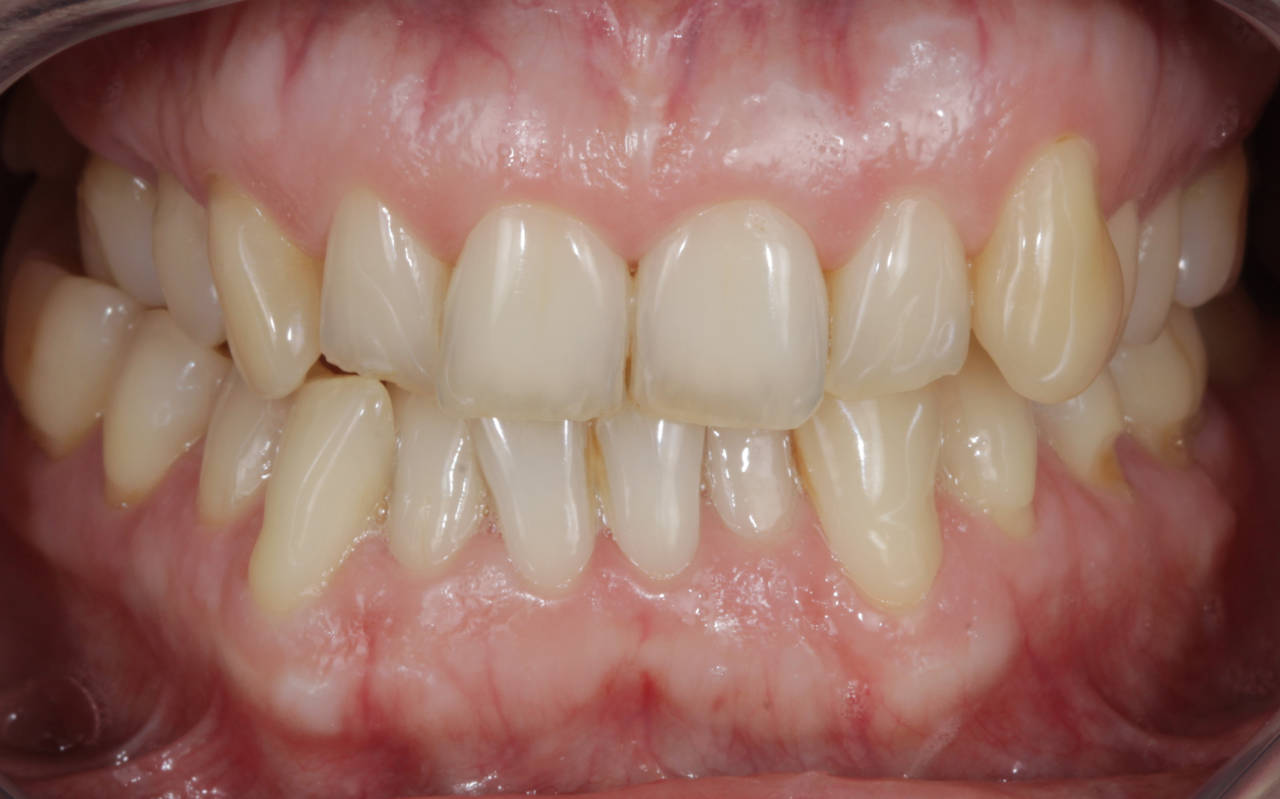

A harmonização do sorriso fez toda a diferença nes